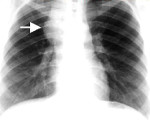

Тератомы данной анатомической зоны диагностируются на основании клинических признаков и данных дополнительных исследований. На рентгенограмме грудной клетки определяется опухолевидное образование округлой формы с четкими границами. Иногда в области тератомы средостения просматриваются плотные включения (зубы, фрагменты костной ткани). КТ органов грудной клетки помогает уточнить структуру и распространенность опухоли. Отсутствие четких границ по данным радиологических исследований рассматривается, как возможный признак малигнизации тератомы средостения.